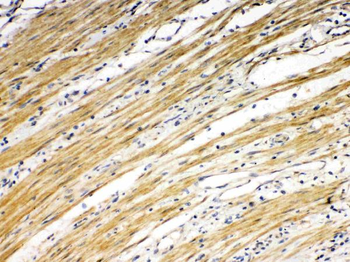

10 μg, 100 μg - Anti-DR5/TNFRSF10B Antibody [orb389514]

FC, IHC, WB

Human, Mouse, Rat

Rabbit

Polyclonal

Unconjugated

10 μg, 100 μg - Anti-Annexin IV/ANXA4 Antibody [orb18546]